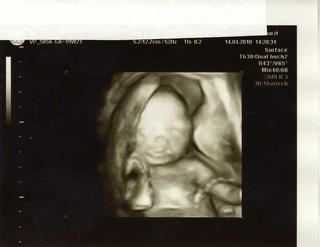

tak hlasim ze mame 2kila nahore, coz nas moc tesi ... cekal jsem vic, ale setricka ze at se nebojim, ze pak se budu jeste hrozit jak pribivaj 😀 ... mrnousek je v poradku, doktor meril hlavicku a myslim ze i telicko, ale jelikoz nic nerikal tak je vse v poradku .... s pritelem jsme se chlamali nad 3D obrazkem, me totiz ten uhel prisel jak kdyz ma nosanek jak prasatko .... jinak nosanek je taky krasnej a rty rostep nemaj, coz me uklidnilo .... doktor rikal ze merit velikost je trosku obtizne, jelikoz je mrnousek uz velky a skrceny, ale rikal ze by jsme meli mit kolem 20cm, uf .... joooo a vypadame na holcicku 😀 nevydel nic co by ukazovalo na chlapecka 🙂

dalsi oftecky dam do alba, ale kdyby jste se do nej zas nedostali, tak tahle je nejlepsi .... 3D 😀

ivus dekuju 😵 ... nechtel rict je to na 100% holcicka, ale do knizecky mi napsal ten kruh s plusem dole, znak pro holku, takze mi to berem ze budem mit holku ... ale s kupovanim ruzovych veci pockam az do kvetna, az to uslysim podruhe zacnu nakupovat 😀 ... delal mi uz utz na brisku, tak jsem si konecne prisla jak tehule 😀 a pritel mohl tentokrat sedet vedle me a koukat s doktorem na obrazovku 😎

schnucki, tak prvně gratulace k ktmou, že je vše ok, to je nejdůležitější. Takže asi holčička jo? 😀 To je super, ty jsou stejně lepší 😀 Uvidíš jak příště, ono to určení holčiček je takové méně jisté..... Navíc když se stydí a neroztáhnou úplně nožičky 😀

blondy dekuju 😵 me prislo ze mela nozky radne rozcapene, i kdyz ja tam chvilema nevidela vubec nic 😀 ... ja jsem pak v aute rikala pritelovi, ze treba je to kluk a ma maleho pindika 😀 ale kdyz to doktor poznamenal do knizecky, tak ted na male mluvime jako na holcicku 🙂

schnucki, tak jestli měla nožičky hezky od sebe tak je to víceméně jasné 😀. Uvidíš jak příště, ale žekla bych , že se to potvrdí, jestli doktor nebyl slepý 😀 Ikdyž on se občas ten pindík fatk může schovat až bůhvíkam. Kamarádka takhle měla i fotku, fakt to vypdalo jako pipinka, i malé stydké pysky tam byly a naknoec z toho byl chlapeček jako hora 😀. Dva dny ho enchtěla, že to není její dítě, že jí ho vyměnili i se chtěla soudit z nemocnicí 😀. Jojo to jsou hold ty hormony a určení pohlaví dle UTZ... 😝 😀 . Zas na druhou stranu tohle jsou fakt jen vyjímky a většinou se ti dkotoř trefí, v 19tt už je mimi dostečně velké 🙂